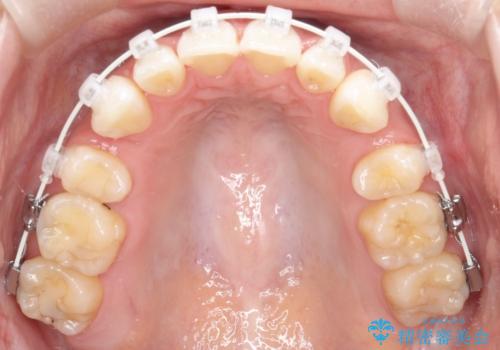

【審美装置】前歯のがたがたを治したい

- 審美装置

- 前歯の凸凹と口元の突出感を主訴に来院されました。

臼歯関係が上顎前突傾向のため、上の小臼歯を抜歯してワイヤー矯正を行なっております。